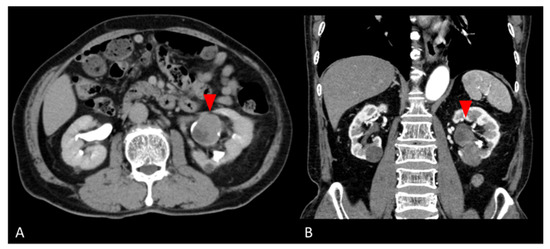

2. Case Presentation

2.1. Clinical Summary

2.2.2. Retroperitoneal Tumor Specimen